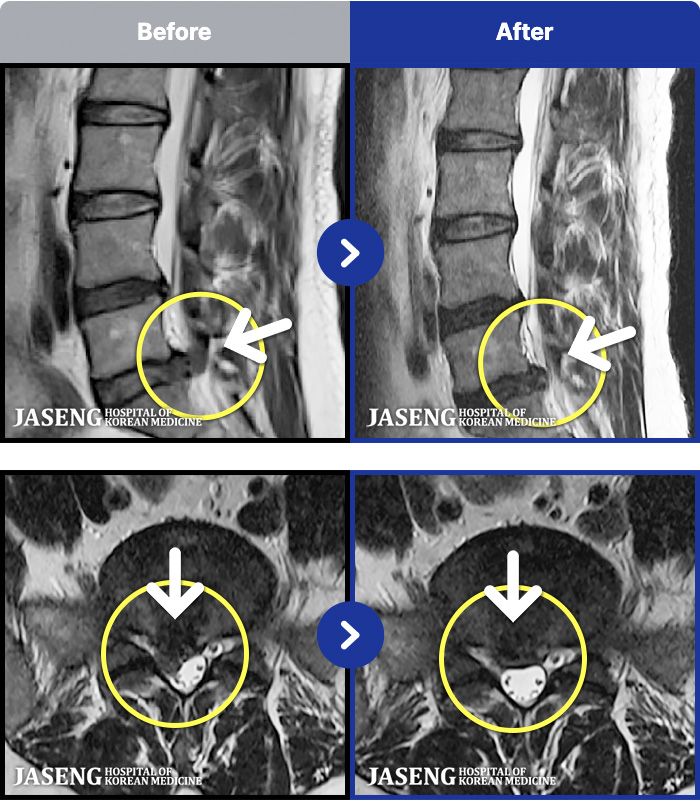

MRI ũ ʸ Ȯϼ.

㸮 ϻ .